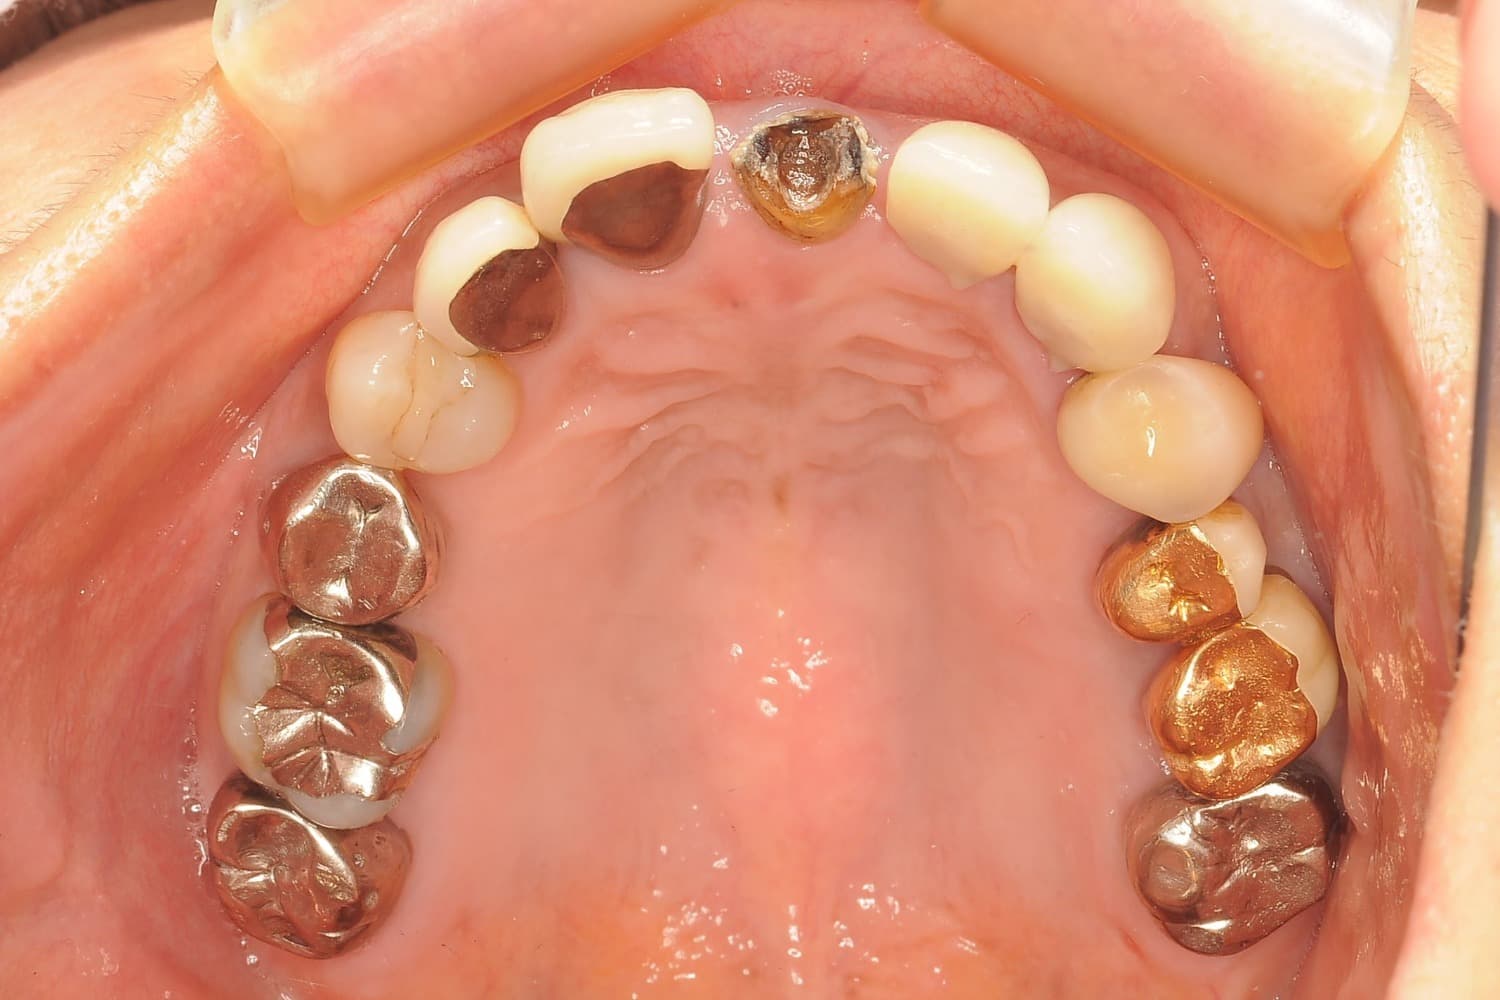

Before

左上6番の抜歯と同時に骨を増やす処置(GBR)を行い、2カ月後の精密検査で土台の回復を確認します。インプラントプレミアムコースで、安全にインプラントを埋入します。

主訴

左上6番に違和感。根尖病巣と歯周病で動揺あり。

手術代580,000円+骨補填材代+上部構造代

副鼻腔炎等の耳鼻科領域の症状が発現することがあります。